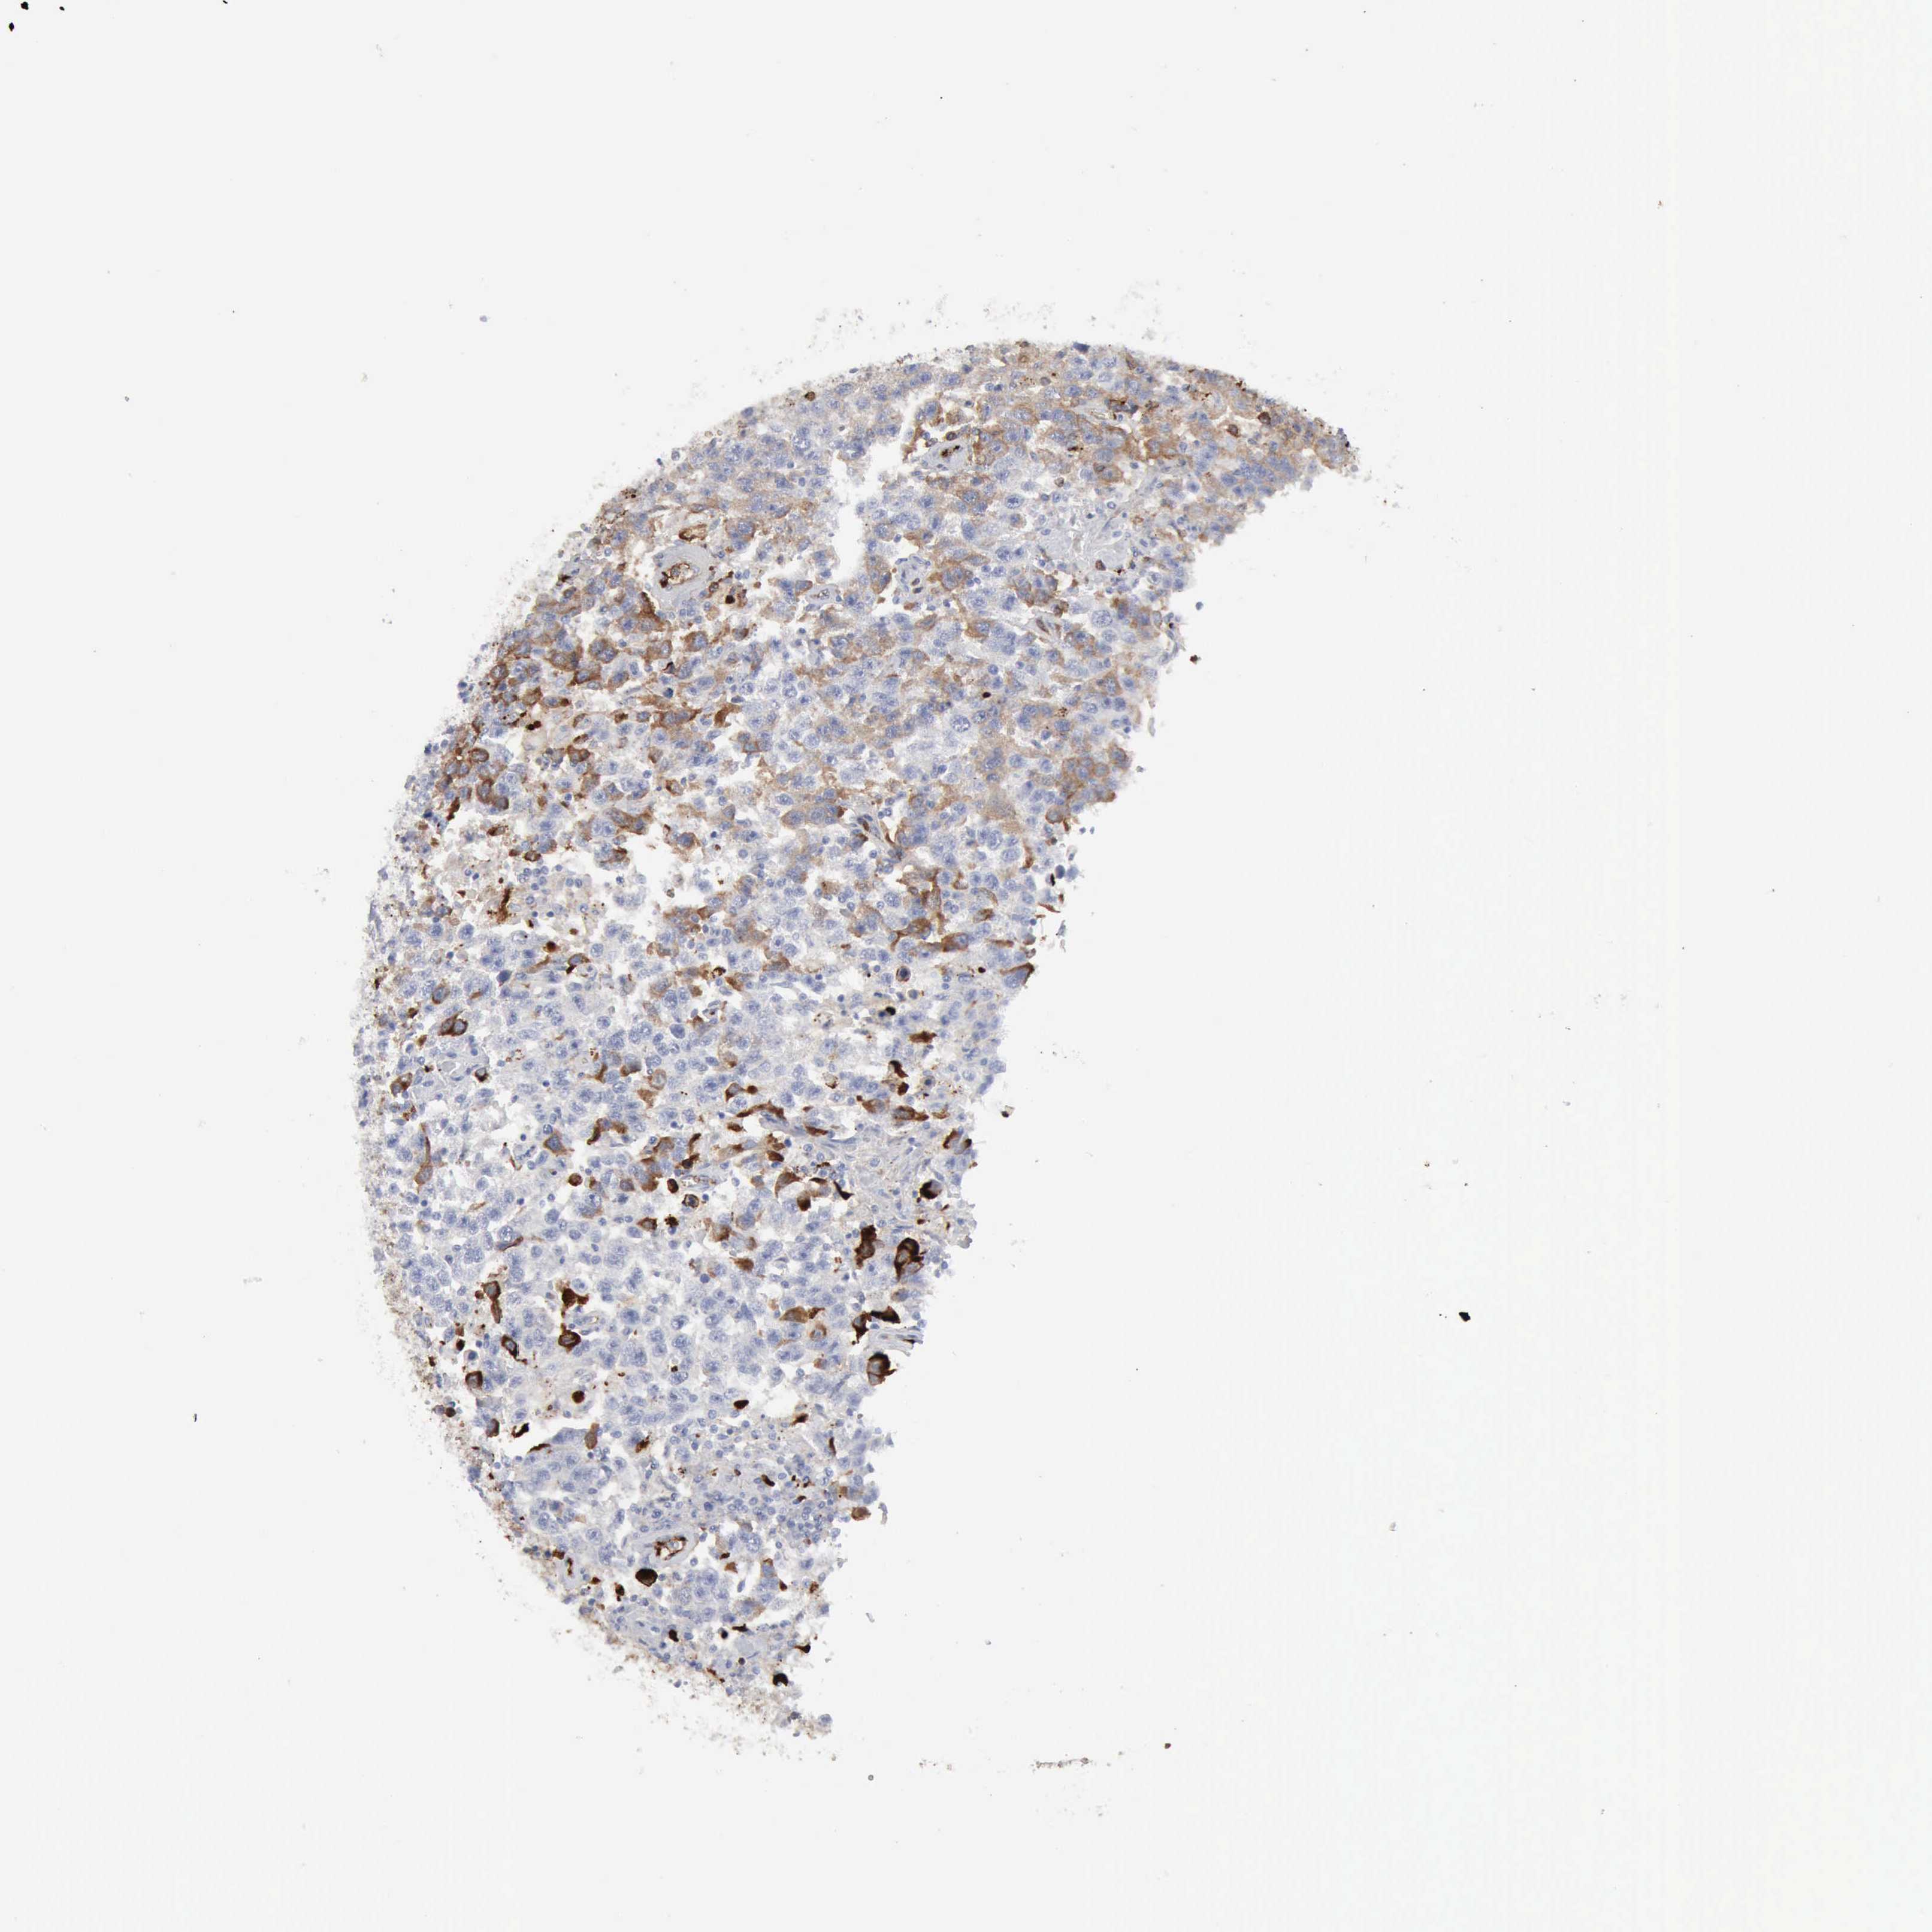

TESTIS CANCER - Protein expressioni

A mouse-over function shows sample information and annotation data. Click on an image to view it in a full screen mode. Samples can be filtered based on level of antibody staining by selecting one or several of the following categories: high, medium, low and not detected. The assay and annotation is described here.

Antibody stainingi

Antibody staining in the annotated cell types in the current human tissue is reported as not detected, low, medium, or high, based on conventional immunohistochemistry profiling in selected tissues. This score is based on the combination of the staining intensity and fraction of stained cells.

Each image is clickable and will lead to virtual microscopy that enables deeper exploration of all samples and also displays staining intensity scores, fraction scores and subcellular localization as well as patient and tissue information for each sample.

Antibody HPA001578

Intensity

Strong

Moderate

Weak

Negative

Quantity

>75%

75%-25%

<25%

None

Location

Nuclear

Cytoplasmic/membranous

Cytoplasmic/membranous,nuclear

Seminoma, NOS

Carcinoma, Embryonal, NOS